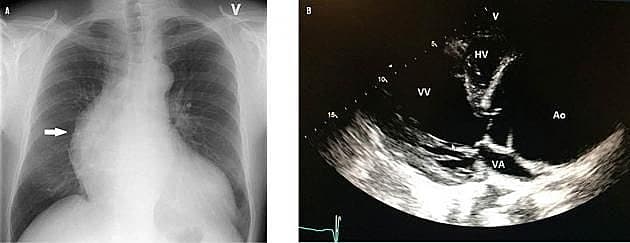

Åndenød og trykken i brystet kan have mange årsager. Hos denne patient gav røntgenoptagelse af thorax mistanke om en sjælden tilstand, hvilket blev bekræftet ved yderligere billeddiagnostiske undersøgelser. Patienten blev opereret med et godt resultat.